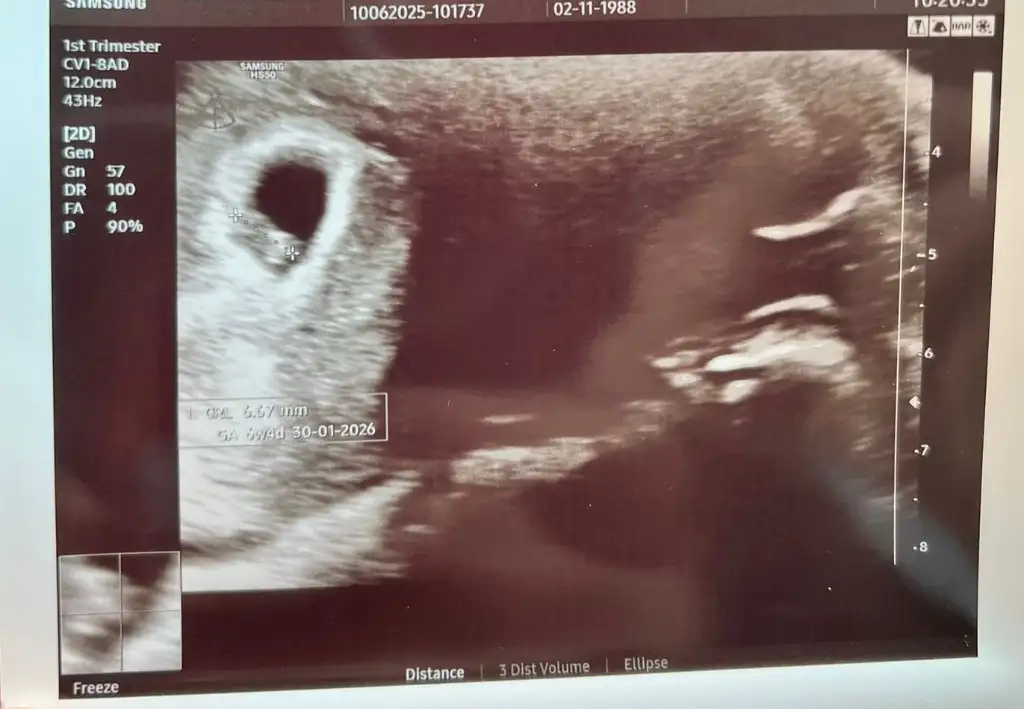

Erkek sanırım doktor bir şey demedi miArkadaşlar benimde ultrason goruntume bakar mısınız 13+4 haftalık cinsiyeti nedir sizce

Doktor ilk erkek gibi sanki dedi ama sonrasında net değil dedi çıkıntı var ama erkek mi kız mı belli değil dedi. 3 hafta sonra artıkErkek sanırım doktor bir şey demedi mi